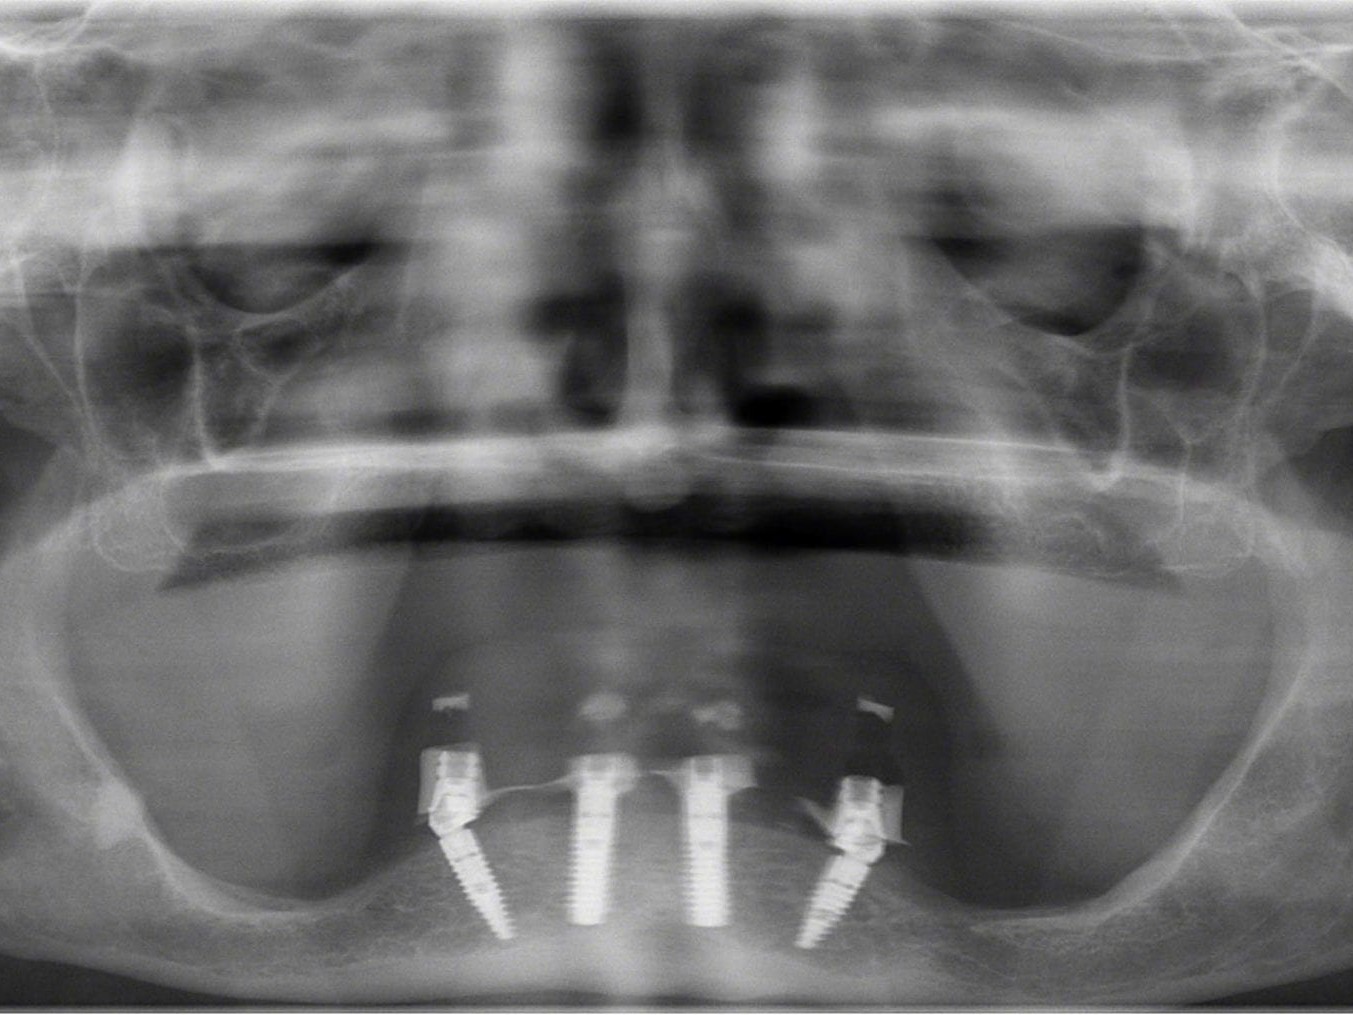

In Lokalanästhesie unter anästhesiologischem Standby mit intravenöser Antibiose mittels Clindamycin 600 mg 2mal/d wurde die Bohrschablone eingesetzt und mit Osteosyntheseschrauben fixiert (Abb. 8). Der Eingriff erfolgte nahezu flapless und somit transgingival. Nun erfolgte die Umsetzung des Straumann Hülse-in-Hülse-Konzeptes. Der Zylinder des Bohrlöffels wird in die an der Bohrschablone fixierten Hülse (Ø 5 mm) in den geplanten Regionen eingeführt. Für jeden Bohrerdurchmesser (Ø 2,2 mm und Ø 2,8 mm) ist ein entsprechender Bohrlöffel erhältlich. Jeder Bohrlöffel besitzt an seinen Enden Zylinder unterschiedlicher Höhe, die entsprechend chirurgischem Protokoll angewendet werden. Es wurden sämtliche Bohrstollen protokollgemäß aufbereitet (Abb. 9-11). Nach der Aufbereitung der Bohrstollen für die angulierten Implantate (Abb. 12-14) wurden die Straumann Bone Level Tapered Implantate (ø 3,3 mm) in regio 035 (Länge 10 mm) und 045 (Länge 12) gesetzt (Abb. 15). Abschließend wurden sämtliche Endpositionen der Implantate in regio 035 und 045 anhand der Lasermarkierungen am Übertragungsteil betreffend ihrer orovestibulären Ausrichtung exakt überprüft (Abb. 16). Nach Entfernung der Einbringhilfen und der Osteosyntheseschrauben konnte die Bohrschablone wieder entnommen werden. In regio 032 und 042 wurden nun die durchmesserreduzierten Straumann NNC (ø 3,3 mm Länge 12 mm) Implantate inseriert (Abb. 17, 18). Bei diesen Implantaten bedurfte es keiner Ausrichtung bezogen auf die orofasziale Ausrichtung. Hier musste die Insertionstiefe bezogen auf das NNC-Implantat beachtet werden (Abb. 19). Die NNC-Implantate wurden mit den entsprechenden Klebebasen versehen (Abb. 20). Danach wurden in regio 035 und 045 auf die Pro Arch Sekundärteile die dazugehörigen Retentionskappen (Abb. 21), die zur Vergrößerung der Oberfläche mit 120 μ Aluminiumoxyd abgestrahlt wurden, eingesetzt. Es erfolgte der typische Naht-Wund-Verschluss mit Einzelknopfnähten. Zum Abschluss erfolgte das prothetische Procedere mit der Eingliederung des Interimszahnersatzes in Okklusion (Abb. 22). Hierfür wurden die Retentionskappen und die Klebebasen mit dem Sofortprovisorium über ein selbsthärtendes fluoreszierendes kaltpolymerisierendes Paste-Paste-Kartuschensystem fixiert, dieser Zahnersatz extraoral versäubert (Abb. 23) und in der Mundhöhle refixiert (Abb. 24). Die Schraubenkanäle wurden mit Kunststoff verschlossen (Abb. 25). Abschließend erfolgte die radiologische Kontrolluntersuchung (Abb. 26).